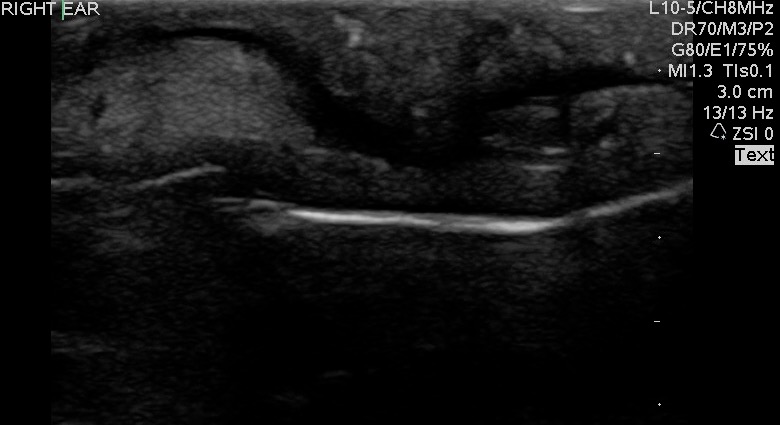

- Figure 1 and 2. Normal Ear

Video 1. Normal Ear - Anterior and posterior skin layers have thin hyperechoic appearance.

- Middle layer containing cartilage appears as a thin hypoechoic band.

- At the antihelix border the cartilage is thicker; the mean thickness is 0.8 ± 0.1 mm (at the middle third of the antihelix in transverse axis).

- At the lobule the mean thickness is 6.9 ± 1 mm.